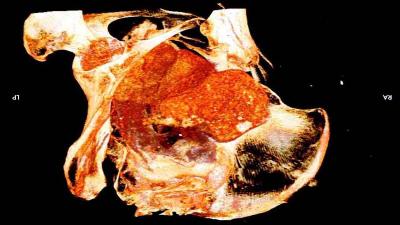

या ममीचे केस लांब होते आणि महिलांची छाती होती. त्यासोबतच या ममीच्या पोटात एक भ्रूणही होतं. आम्ही पोटात छोटे हात आणि पाय पाहिले. हा शोध आमच्यासाठी हैराण करणारा आणि आनंद देणारा होता. मारजेनाने सांगितले की, आम्हाला असं वाटतं की, ही गर्भवती महिला २० ते ३० वयाची असेल.

ममीच्या पोटातील भ्रूणाच्या डोक्याचा आकार दिसून येतो. ज्यावरून असं वाटतं की, हे भ्रूण २६ ते २८ आठवड्यांचं असेल. वॉरसॉ नॅशनल म्युझिअम येथील ममी प्रोजेक्टमध्ये या ममीची टेस्ट केली गेली. याचा रिपोर्ट जर्नल ऑफ आर्किओलॉजिकल सायन्समध्ये प्रकाशित झाला.